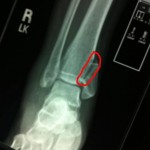

I have received many emails and messages from my wonderful readers, so I wanted to take the time to sit down and explained what happened to me! Broken bones are thankfully something I have never had to deal with. I made it through childhood and adolescence with not a single bone and thankfully (knock on wood) thus far none of my children have experienced anything broken either. Well all that came crashing, or should I say falling down Thursday evening as I tumbled down an entire flight of stairs holding my 18 month old! My main concern the entire way down was not landing on him! Babies … [Read more...]